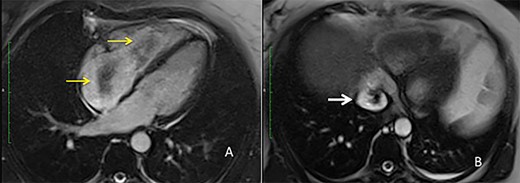

A 52-year-old woman was transferred to our department with a diagnosis of right atrial thrombus and mild right cardiac insufficiency. Her complaint was due to a mass in her IVC extending through the right atrium and abutting in the right ventriculum, highly suspect for a thrombus. CT scan revealed a mass arising from the right adnexa that via the right densely enhancing vascular structures of the ovarian veins reached the IVC and right atrium forming the intracardiac mass (Fig. 1). The preoperative work-up consisted of transoesophageal ultrasonography that showed a free-floating echogenic right intraatrial mass measuring 70 × 50 mm originating from the IVC and protruding in the right ventriculum through the tricuspid valve. Cardiac MRI confirmed the presence and features of the mass (Fig. 2).

MRI view (A) right atrium with the intravascular leiomyoma prolapsing into the right ventricle (yellow arrow) (B) intrahepatic inferior vena cava stored with the intravascular leiomyoma (white arrow).